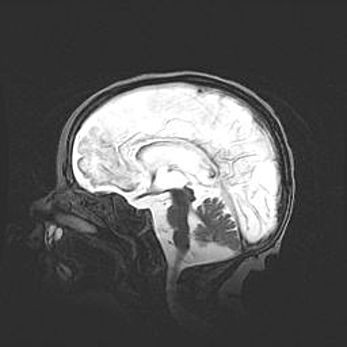

Сообщающаяся гидроцефалия. Кистозная энцефаломаляция головного мозга.

Возраст: 3 месяца 4 дня

Вес: 3100 г

Пол: женский

Окружность головы: 34 см

Срок гестации: 31 неделя

Кистозная энцефаломаляция головного мозга - одна из форм поражения головного мозга в детском возрасте. Характеризуется возникновением множественных и распространённых кист в коре, белом веществе и подкорковых образованиях головного мозга у плодов, новорождённых и детей раннего возраста. Развитие кистозной энцефаломаляции связано с внутриутробной асфиксией и гипотонией, родовой травмой, тромбозом синусов, пороками развития сосудов, инфекциями, сепсисом и другими причинами. Наиболее значимые инфекционные агенты: вирусы простого герпеса, цитомегалии, краснухи, токсоплазмы, энтеробактерии, золотистый стафилококк и другие.